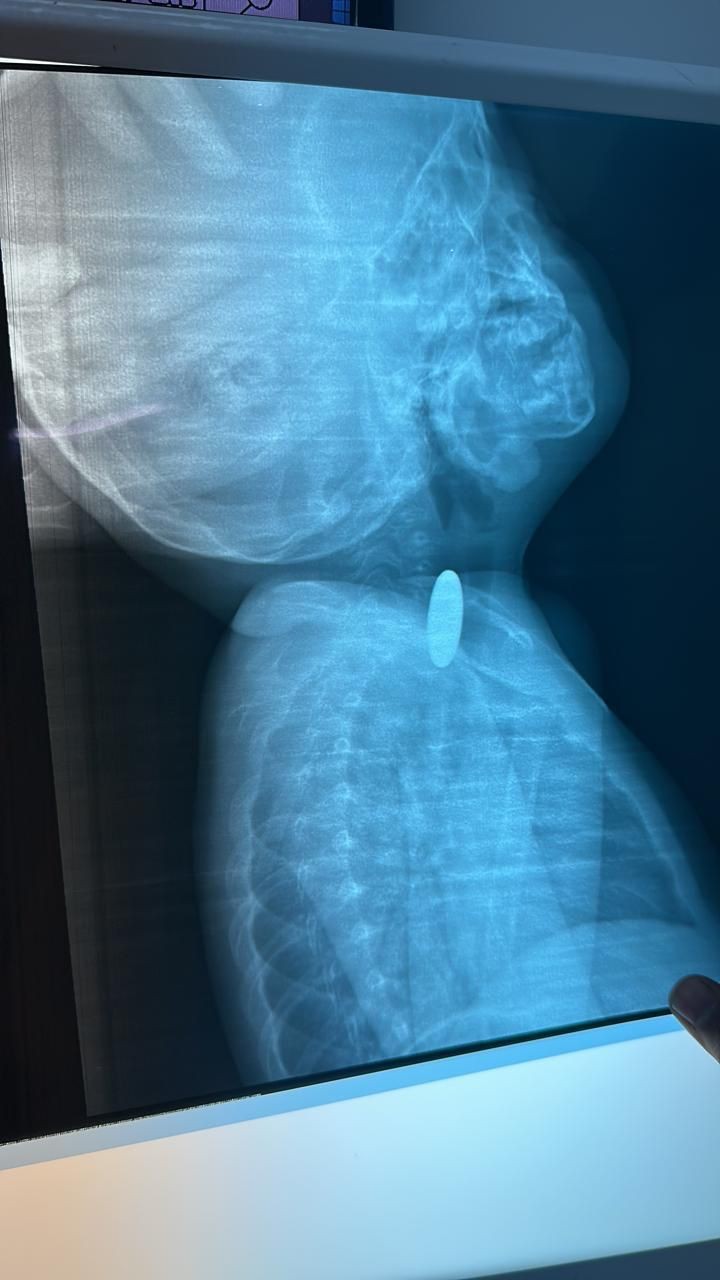

تمكن - بفضل الله - فريق طبي بمستشفى رابغ العام من استخراج قطعة معدنية من بلعوم طفل يبلغ من العمر عامان خلال عملية لم تستغرق أكثر من 10 دقائق.

وأوضحت (صحة جدة) أن الطفل قَدِم إلى طوارئ المستشفى وهو يشكو ابتلاع جسم غريب (قطعة نقود معدنية) كانت قد علقت في منطقة البلعوم؛ مما تسبب في اختناق وعدم قدرة على البلع؛ حيث قرر الطاقم الطبي إجراء عملية عاجلة بالمنظار لإزالة الجسم الغريب، والتي تبين أنها قطعة معدنية نقدية، وقد كُللت العملية بالنجاح  دون حدوث مضاعفات - ولله الحمد - وقد غادر الطفل المستشفى وهو بصحة جيدة.